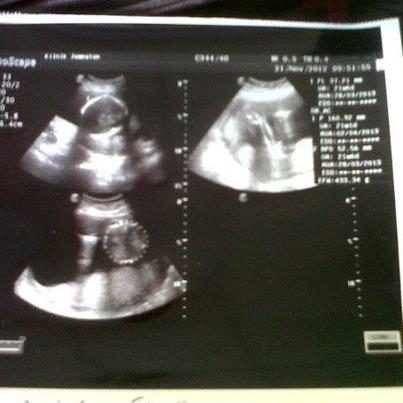

alhamdulillah bb dh masuk 22W hari ni

insyaAllah yul akan dpt bb girl

due date 28hb mac 2012

berat bb skrg dlm 500gram